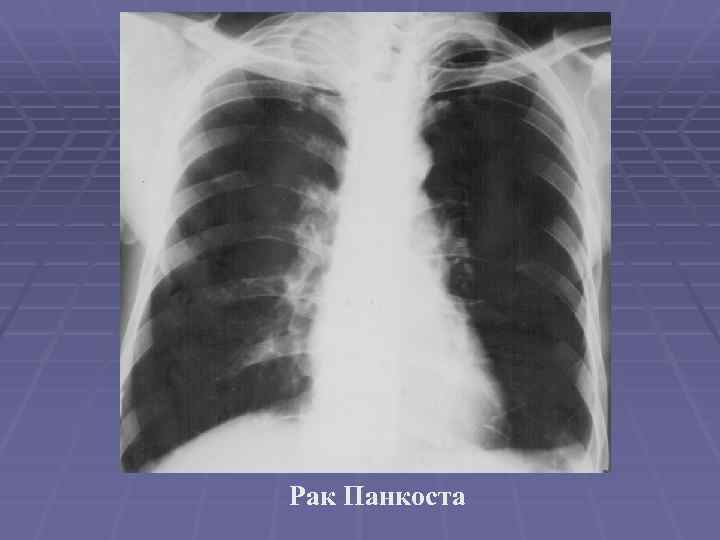

Рентгеновские снимки опухоли Панкоста